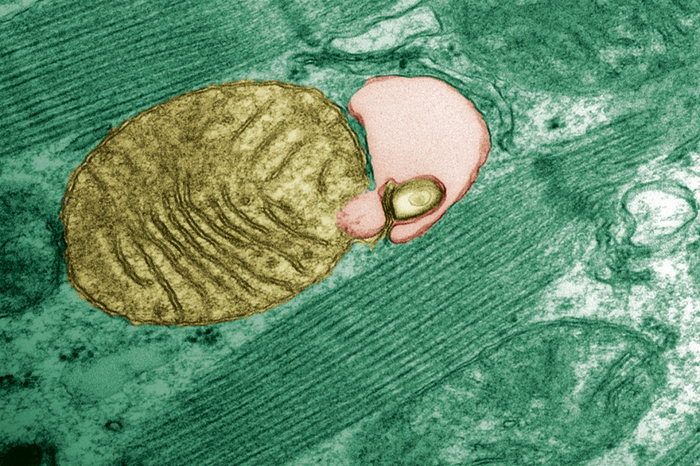

图:线粒体被自噬小体吞噬

来源:Júlio C. B. Ferreira/USP